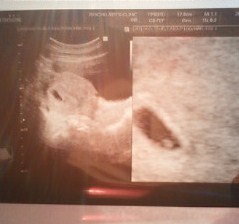

4w0dの、おなかの上にプローブを当てる経腹プローブの写真です。矢印が胎嚢かな?というところです。その後、5w0dに胎嚢確認できました。